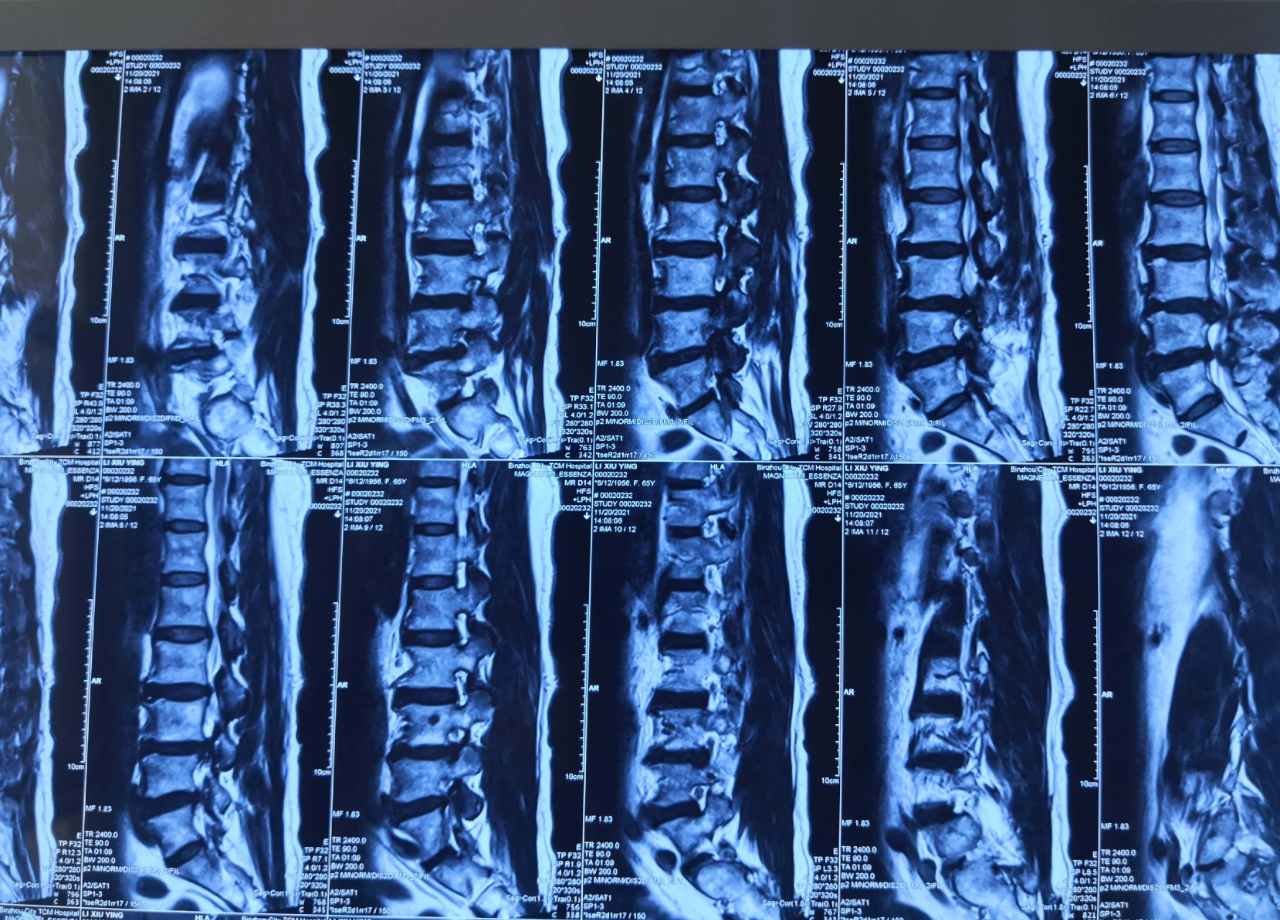

患者李某,女性,65岁。

主诉:腰部疼痛20余年,加重伴右下肢无力3年。间歇性跛行,跛距大约100米。

查体:腰椎生理曲度改变,L3/4/5棘突间及双侧压痛明显,叩击痛(+),无明显放射痛。屈颈试验(+),仰卧挺腹试验(+),直腿抬高试验右50°(+)左70°(-),股神经牵拉试验左(-)右(-),“4”字试验左(-)右(-)。右下肢肌力稍减弱,皮肤感觉正常,双侧膝腱反射(++),双侧跟腱反射(++),双侧BabinskiSign(-)。

诊断:1.腰椎椎管狭窄(L3/4) 2.腰椎滑脱(L3 I°)。